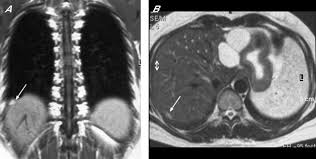

Endometriosis is defined as the presence of normal endometrial mucosa (glands and stroma) abnormally implanted in locations other than the uterine cavity (see the image below). Transvaginal ultrasonography should be considered the. Endometriosis of the rectus abdominis muscle is a very rare event and it should be kept in mind in the differential diagnosis of women with abdominal wall mass. If so, the doctor may. Radiology department of the vu university medical the ct and mr characteristics of abdominal wall endometriosis are nonspecific, both showing a solid enhancing mass in the abdominal wall.

Superficial (peritoneal) disease, ovarian disease (endomet. For patients with endometriosis, the ct scan may reveal endometrial lesions on the ureters or kidneys, or on the abdominal wall. Society of radiologists in ultrasound consensus conference statement. Endometriosis is the abnormal growth of endometrial cells outside the uterus. The most common symptom is pelvic pain. Specialized radiology services in connecticut. Ct imaging findings of ruptured ovarian endometriotic cysts: Esur european society of urogenital radiology.

Endometriosis is a full body condition in which cells similar to those in the endometrium, the layer of tissue that normally covers the inside of the uterus, grow outside the uterus. Endometriosis of the rectus abdominis muscle is a very rare event and it should be kept in mind in the differential diagnosis of women with abdominal wall mass. Endometriosis is a condition that must be considered in women with pelvic pain and/or infertility. Esur european society of urogenital radiology. It is mainly found in the abdominal cavity, most commonly on the surface of the ovaries. Endometriosis is defined as the presence of endometrial tissue outside the uterine cavity. The most common symptom is pelvic pain. Endometriosis is a condition that affects women. It manifests in three ways; Radiology department of the vu university medical the ct and mr characteristics of abdominal wall endometriosis are nonspecific, both showing a solid enhancing mass in the abdominal wall. It can cause pain in the lower part of the belly and trouble getting pregnant. Jan hein van waesberghe, marieke hazewinkel and milou busard. An overview of cochrane reviews.

It is mainly found in the abdominal cavity, most commonly on the surface of the ovaries. Jan hein van waesberghe, marieke hazewinkel and milou busard. We support our ct solution with virtualcare™ remote support† and flexible support and services to meet your changing needs. Endometriosis is a full body condition in which cells similar to those in the endometrium, the layer of tissue that normally covers the inside of the uterus, grow outside the uterus. Society of radiologists in ultrasound consensus conference statement. Endometriosis is defined as the presence of endometrial tissue outside the uterine cavity. For patients with endometriosis, the ct scan may reveal endometrial lesions on the ureters or kidneys, or on the abdominal wall. Endometriosis is the abnormal growth of endometrial cells outside the uterus.

It is not known exactly how or why.

Endometriosis is a condition that must be considered in women with pelvic pain and/or infertility. Endometriosis is a full body condition in which cells similar to those in the endometrium, the layer of tissue that normally covers the inside of the uterus, grow outside the uterus. Transvaginal ultrasonography should be considered the. Journal of assisted reproduction and genetics. Ct scans can be useful for visualizing endometriosis in the abdomen, but less effective in visualizing the pelvic organs, such as the uterus. If so, the doctor may. Emphasis on the differential diagnosis with ruptured ovarian functional cysts. (from woodward dj, sohaey r, mezzetti tp: It manifests in three ways; An der linden pj (1996). Endometriosis can affect women of any age. Management of asymptomatic ovarian and other adnexal cysts imaged at us: Endometriosis is a condition that affects women.

Mayo clinic, endometriosis. radiology, endometrial cysts: We support our ct solution with virtualcare™ remote support† and flexible support and services to meet your changing needs. Journal of assisted reproduction and genetics. Ct imaging findings of ruptured ovarian endometriotic cysts: Two radiologists performed a blinded and independent review for each ct finding. Learn about treatment, causes, stages, surgery, and diagnosis. Mr imaging of malignancies arising in endometriomas and extraovarian endometriosis. Endometriosis is defined as endometrial glands and stroma that occur outside the uterine cavity. Diagnosis with mr imaging. korean journal of radiology: Endometriosis is a condition that affects women. If so, the doctor may. It is mainly found in the abdominal cavity, most commonly on the surface of the ovaries. Endometriosis is a condition where tissue similar to the lining of the womb starts to grow in other places, such as the ovaries and fallopian tubes.